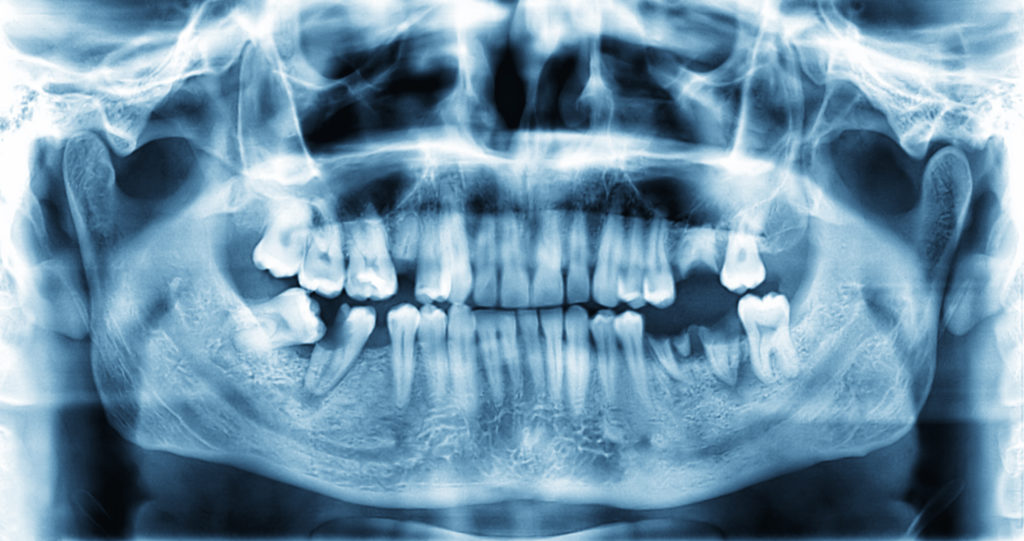

Примеры ортопантомограмм и их анатомия

Раздел: Фотоэссе